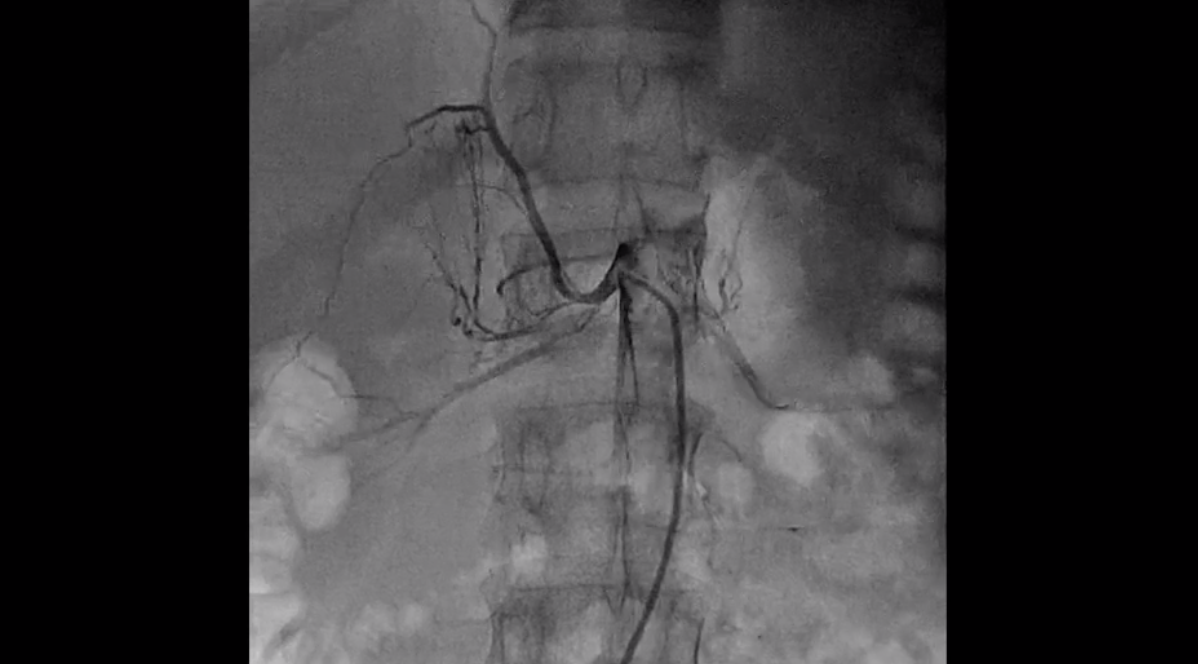

Video Complex Right renal artery stenosis femoral approach for renal Renal Artery Stents In this procedure, doctors widen. renal artery stenosis is the narrowing of one or more arteries that carry blood to your kidneys (renal arteries). renal ostial stenting (ros) is the most common endovascular intervention for treatment of atherosclerotic renal artery. renal artery stenosis (ras) occurs when the arteries that carry blood to your kidneys narrow. renal. Renal Artery Stents.